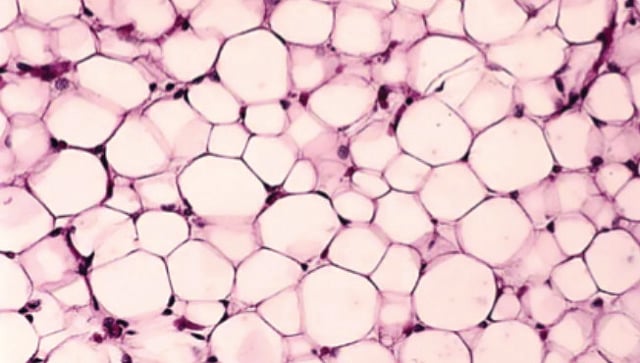

मानवी शरीरात नवीन प्रकारच्या चरबी पेशींचा शोध

या पेशी लठ्ठपणाशी संबंधित असू शकतात

वॉशिंग्टन : माणसाला अद्यापही आपल्याच शरीराची पूर्ण माहिती नाही. त्यामुळेच वेळोवेळी आतापर्यंत अज्ञात असलेल्या काही अवयवांचा शोध लागत असतो. आता शास्त्रज्ञांनी मानवी शरीरात चरबीच्या अनोख्या उपप्रकारांचा शोध घेतला आहे. त्यांच्या कार्यप्रणाली समजून घेतल्यावर असे आढळले की या पेशी लठ्ठपणाशी संबंधित असू शकतात.

‘नेचर जेनेटिक्स’ या वैज्ञानिक जर्नलमध्ये नुकत्याच प्रकाशित झालेल्या या संशोधनामुळे लठ्ठपणाच्या परिणामांवर, जसे की जळजळ, सूज किंवा इन्सुलिन रेझिस्टन्स, नियंत्रण ठेवण्यासाठी नवीन उपचार विकसित करण्याचा मार्ग मोकळा होऊ शकतो, असे शास्त्रज्ञांचे मत आहे. ‘या चरबीच्या उपप्रकारांचा शोध लागणे हे खूपच आश्चर्यकारक आहे,’ असे या संशोधनाच्या सहलेखिका आणि बेन-गुरियन युनिव्हर्सिटी ऑफ नेगेव येथील संगणकीय जीवशास्त्राच्या प्राध्यापिका एस्ती येगर-लोतेम यांनी सांगितले. ‘यामुळे भविष्यात संशोधनाच्या अनेक संधी उपलब्ध होऊ शकतात.‘चरबी पेशी’ या पूर्वीच्या समजुतीपेक्षा जास्त गुंतागुंतीच्या आणि विविध प्रकारच्या असतात, असे कॉर्नेल विद्यापीठाचे पोषण विज्ञानाचे प्राध्यापक डॅनियल बेरी यांनी नमूद केले.

संशोधकांनी असेही लक्षात घेतले आहे की, शरीरातील सर्व प्रकारच्या चरबी समान नसतात. उदाहरणार्थ, पोटाच्या आतील अवयवांजवळ साठणारी व्हिसेरल चरबी ही त्वचेखालील (सबक्युटेनियस) चरबीपेक्षा अधिक धोकादायक असते. व्हिसेरल चरबीमुळे हृदयविकाराचा झटका, स्ट्रोक, मधुमेह, यकृताच्या समस्या आणि इन्सुलिन रेझिस्टन्सचा धोका वाढतो. चरबी पेशींमध्ये नक्की काय घडते हे समजून घेण्यासाठी येगर-लोतेम आणि त्यांच्या सहकार्‍यांनी ‘सेल अ‍ॅटलास’ तयार केला, जो मानवी शरीरातील सर्व पेशींचे नकाशे तयार करण्याच्या जागतिक प्रकल्पाचा एक भाग आहे. संशोधकांनी सिंगल-न्युक्लियस ठछअ सिक्वेन्सिंग तंत्रज्ञानाचा वापर करून चरबी पेशींचे मॅपिंग केले. यामध्ये त्यांनी पेशींच्या ‘आरएनए’चा अभ्यास केला, जो त्या पेशींच्या कार्यक्षमतेबाबत महत्त्वाची माहिती पुरवतो. 15 लोकांच्या पोटातील चरबीच्या पेशींच्या नमुन्यांचे परीक्षण करताना, संशोधकांना आढळले की बहुतांश चरबी पेशी पारंपरिक स्वरूपाच्या होत्या. त्यांचे मुख्य कार्य अतिरिक्त ऊर्जा साठवणे हे होते. मात्र, काही प्रमाणात ‘नॉन-क्लासिकल’ चरबी पेशी आढळल्या, ज्या ऊर्जा साठवण्याव्यतिरिक्त इतर कार्येही करत होत्या. गेल्या काही दशकांत संशोधनाने हे सिद्ध केले आहे की चरबी ऊती फक्त ऊर्जा साठवण्याचे काम करत नाहीत, तर त्या मेंदू, स्नायू आणि यकृताशी संवाद साधत शरीरातील चयापचय, भूक आणि वजन यांचे नियंत्रण करतात. त्यामुळे, चरबी ऊतींमध्ये काही गडबड झाल्यास, त्याचा शरीरातील इतर भागांवरही परिणाम होऊ शकतो, असे येगर-लोतेम यांनी सांगितले.